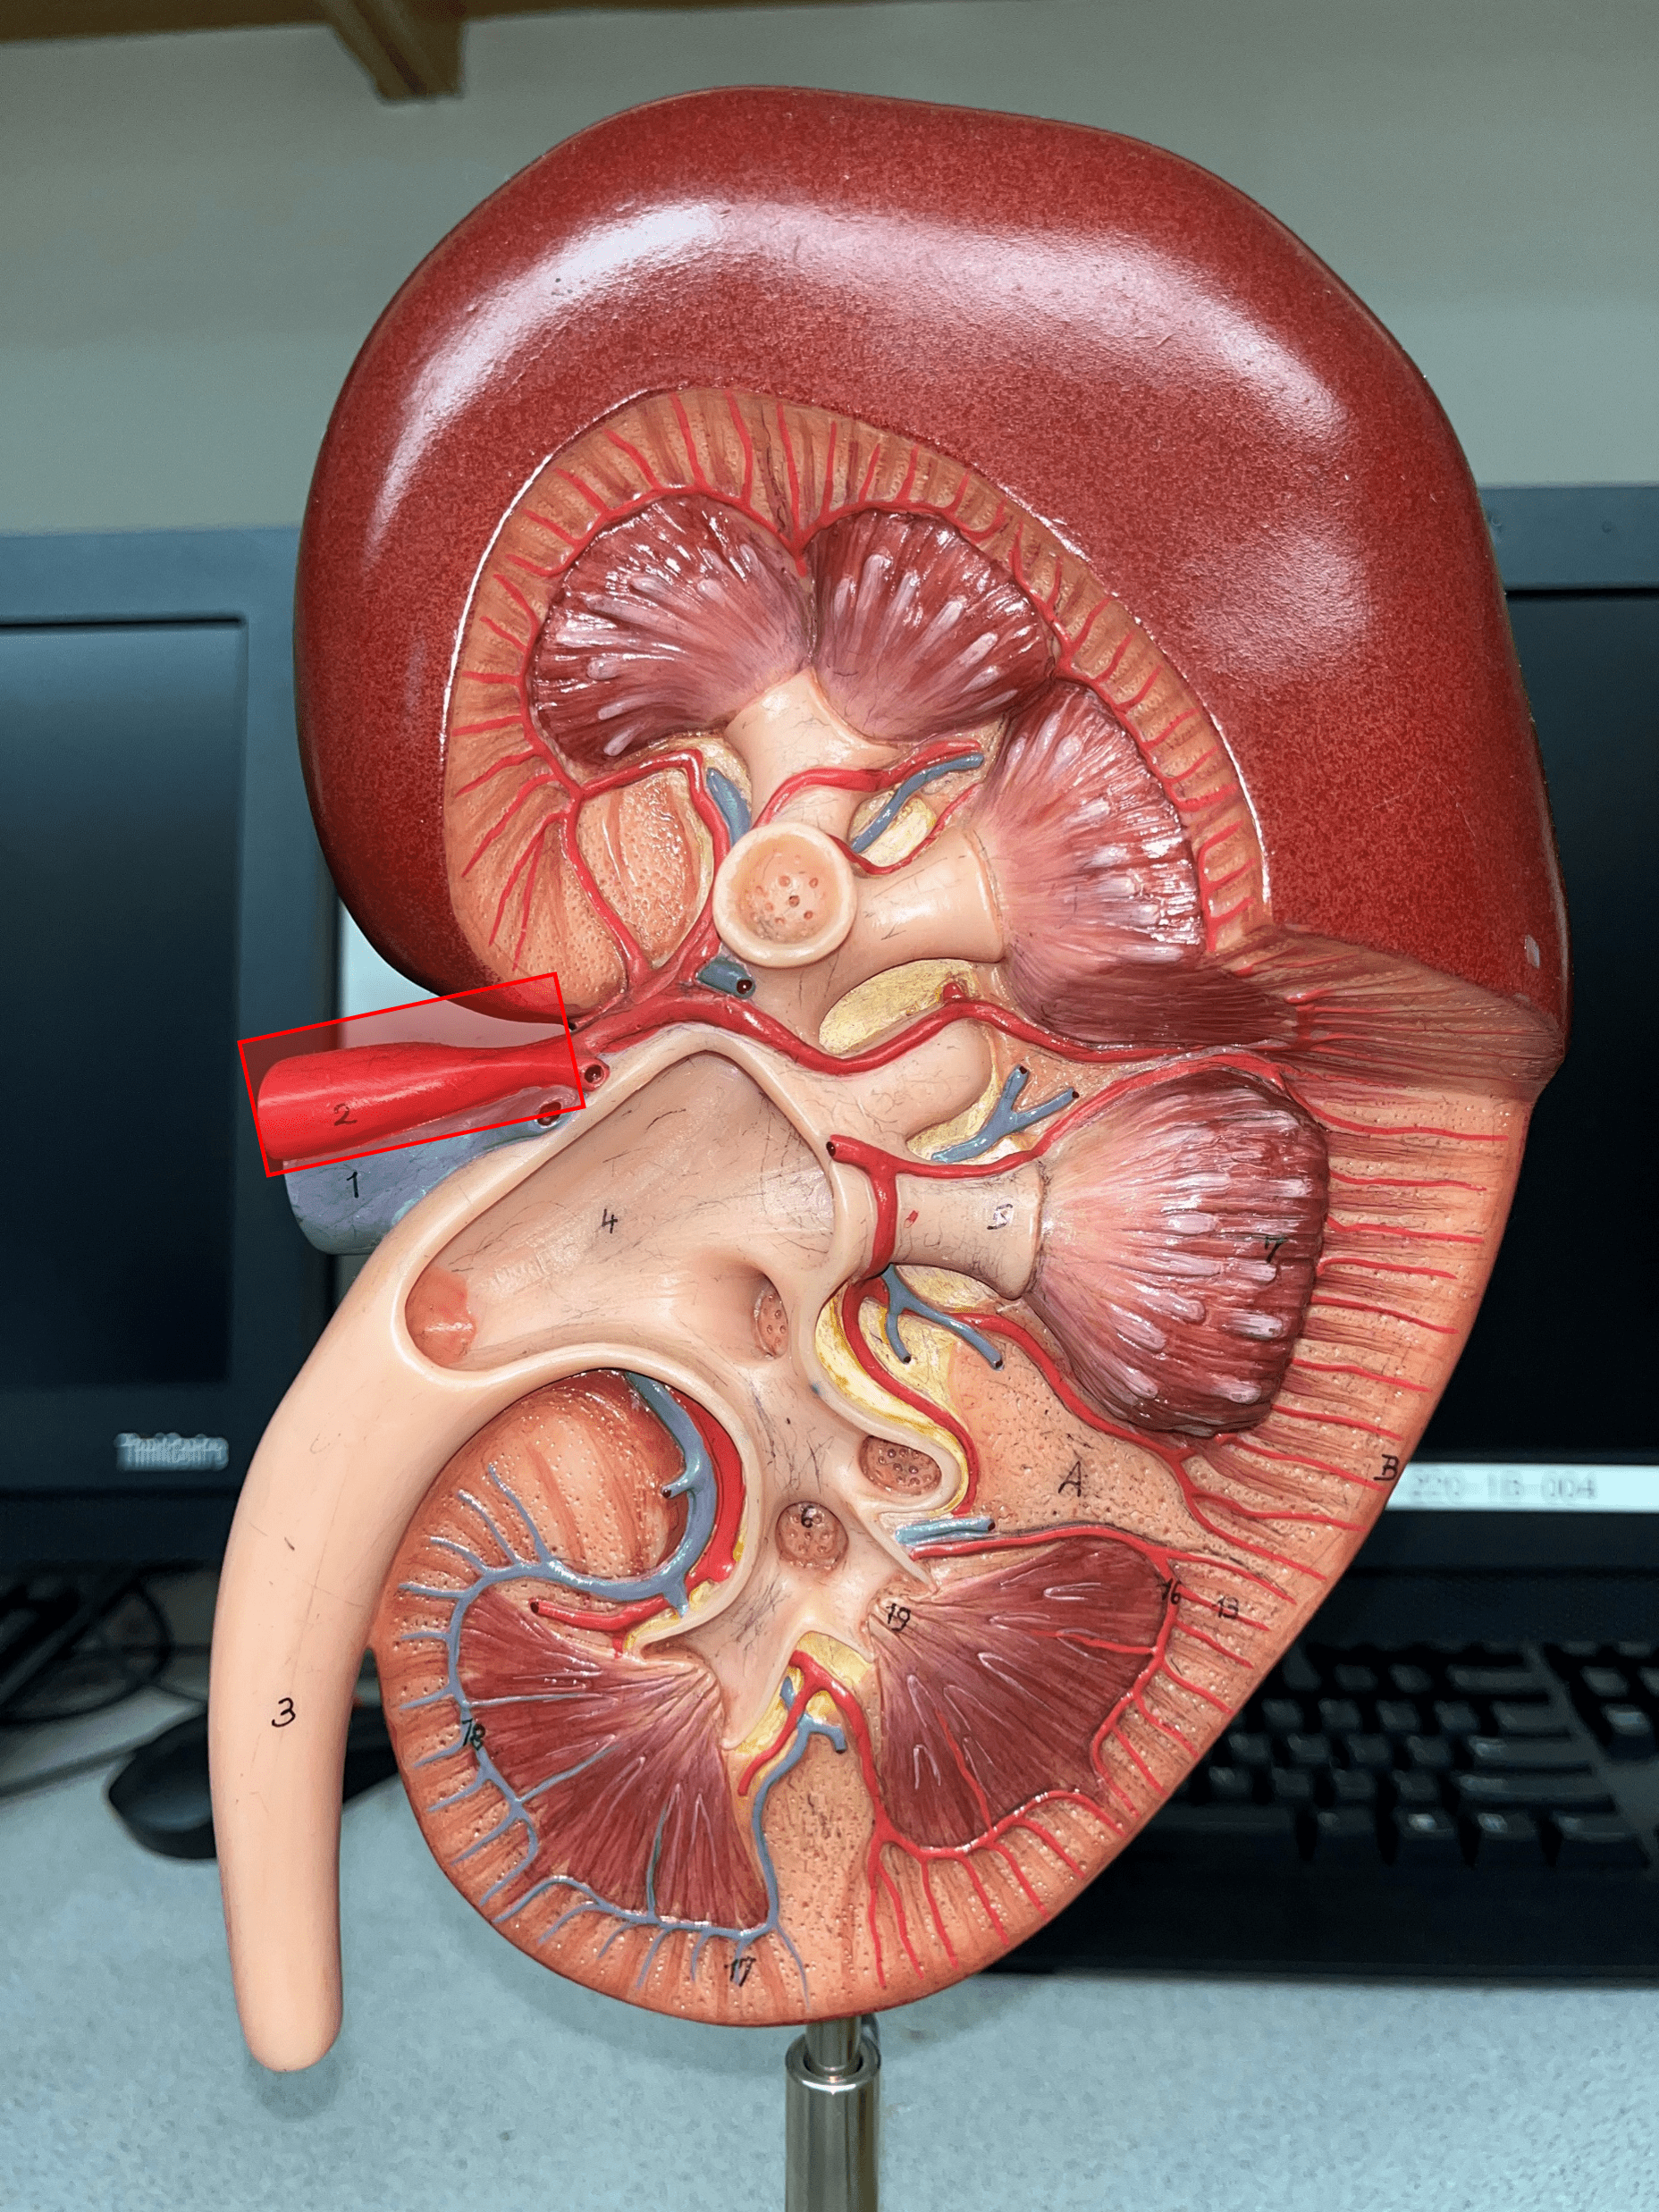

The organ that filters blood and excretes waste as urine.

2

New cards

renal capsule

The thin outer shell of the kidney.

renal artery

• The largest a. of the kidney.

• Supplies the entire kidney.

• Branches into smaller segmental aa.

• Supplies the entire kidney.

• Branches into smaller segmental aa.